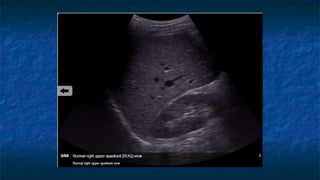

2)FAST: RUQ exam

 Probe placed

 Perpendicular

 Mid-coronal plane

 Just superior to the iliac crest

 Probe facing

 Toward patient’s head

 Evaluating

 Hepatorenal interface

 Possibility of fluid in Morison’s

pouch ( Right Supramesocolic

space)

FAST: RUQ exam

 Normal Anatomy

 In the supine patient, the

hepatorenal space

(Morison’s Pouch) is the

most dependent space

Anterior

Posterior

Inferior

Superior

Morison’s

Pouch